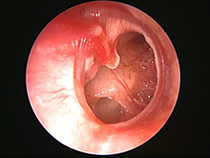

Attikoantrotomie, Rekonstruktion mit Attikspange (As) und Knochenchips (KC), A = Amboss